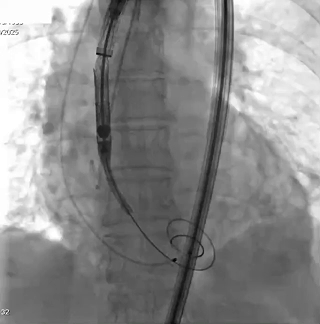

二、手术关键步骤:

猪尾导管进窦

输送器跨过瓣膜,定位件入窦